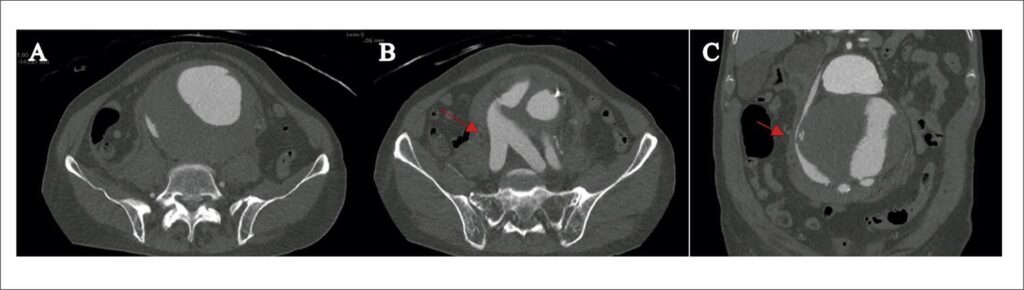

A fístula aortocaval é uma complicação rara do aneurisma de aorta, ocorrendo em cerca de 0,2% a 6,04% de todos os aneurismas de aorta abdominal. Pode ocorrer no contexto de ruptura de aneurisma de aorta, aortite, síndrome de Ehlers-Danlos, síndrome de Marfan ou trauma abdominal penetrante., Os sinais clínicos clássicos são dor abdominal, frêmito abdominal e sintomas de insuficiência cardíaca descompensada. O diagnóstico é geralmente realizado por meio de uma angiotomografia computadorizada, sendo alguns achados típicos: realce precoce do contraste da veia cava inferior (anterior à contrastação do parênquima renal e hepático) e realce retrógrado das veias renais ou ilíacas. O tratamento cirúrgico aberto tem alta morbidade e mortalidade associadas, com taxas relatadas em torno de 30%. Com o advento da terapia endovascular essas taxas foram reduzidas, com taxas de sucesso de até 96%.

Paciente sexo masculino, 85 anos, hipertenso e ex-tabagista, deu entrada na unidade de emergência com história de início de dor abdominal súbita há quatro dias, associada a massa abdominal pulsátil em região de hipogástrio. Foi realizada angiotomografia de aorta total, sendo evidenciado aneurisma de aorta abdominal pararrenal com diâmetro de 11,5 cm, estendendo-se a partir da artéria renal direita até bifurcação aórtica, com sinais de rotura tamponada para retroperitônio (), associado à fístula aortocaval com ponto de comunicação ao nível das ilíacas. Na imagem de tomografia foi observado o realce retrógrado e precoce das ilíacas na fase arterial ( e ). Durante avaliação clínica, paciente apresentou instabilidade hemodinâmica, sendo indicado procedimento cirúrgico de emergência. No intraoperatório () foi evidenciado aneurisma com sinais de rotura, apresentando frêmito à palpação. Paciente evoluiu com hipotensão refratária e óbito.